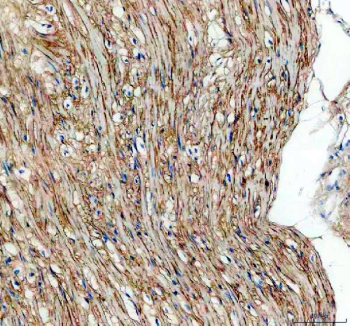

Immunohistochemical staining of TGFBI using anti-TGFBI antibody. TGFBI was detected in a paraffin-embedded section of human intestinal smooth muscle tissue. Heat mediated antigen retrieval was performed in EDTA buffer (pH 8.0, epitope retrieval solution). The tissue section was blocked with 10% goat serum. The tissue section was then incubated with 2 ug/ml rabbit anti-TGFBI antibody overnight at 4oC. Peroxidase Conjugated Goat Anti-rabbit IgG was used as secondary antibody and incubated for 30 minutes at 37oC. The tissue section was developed using an HRP secondary and DAB substrate.